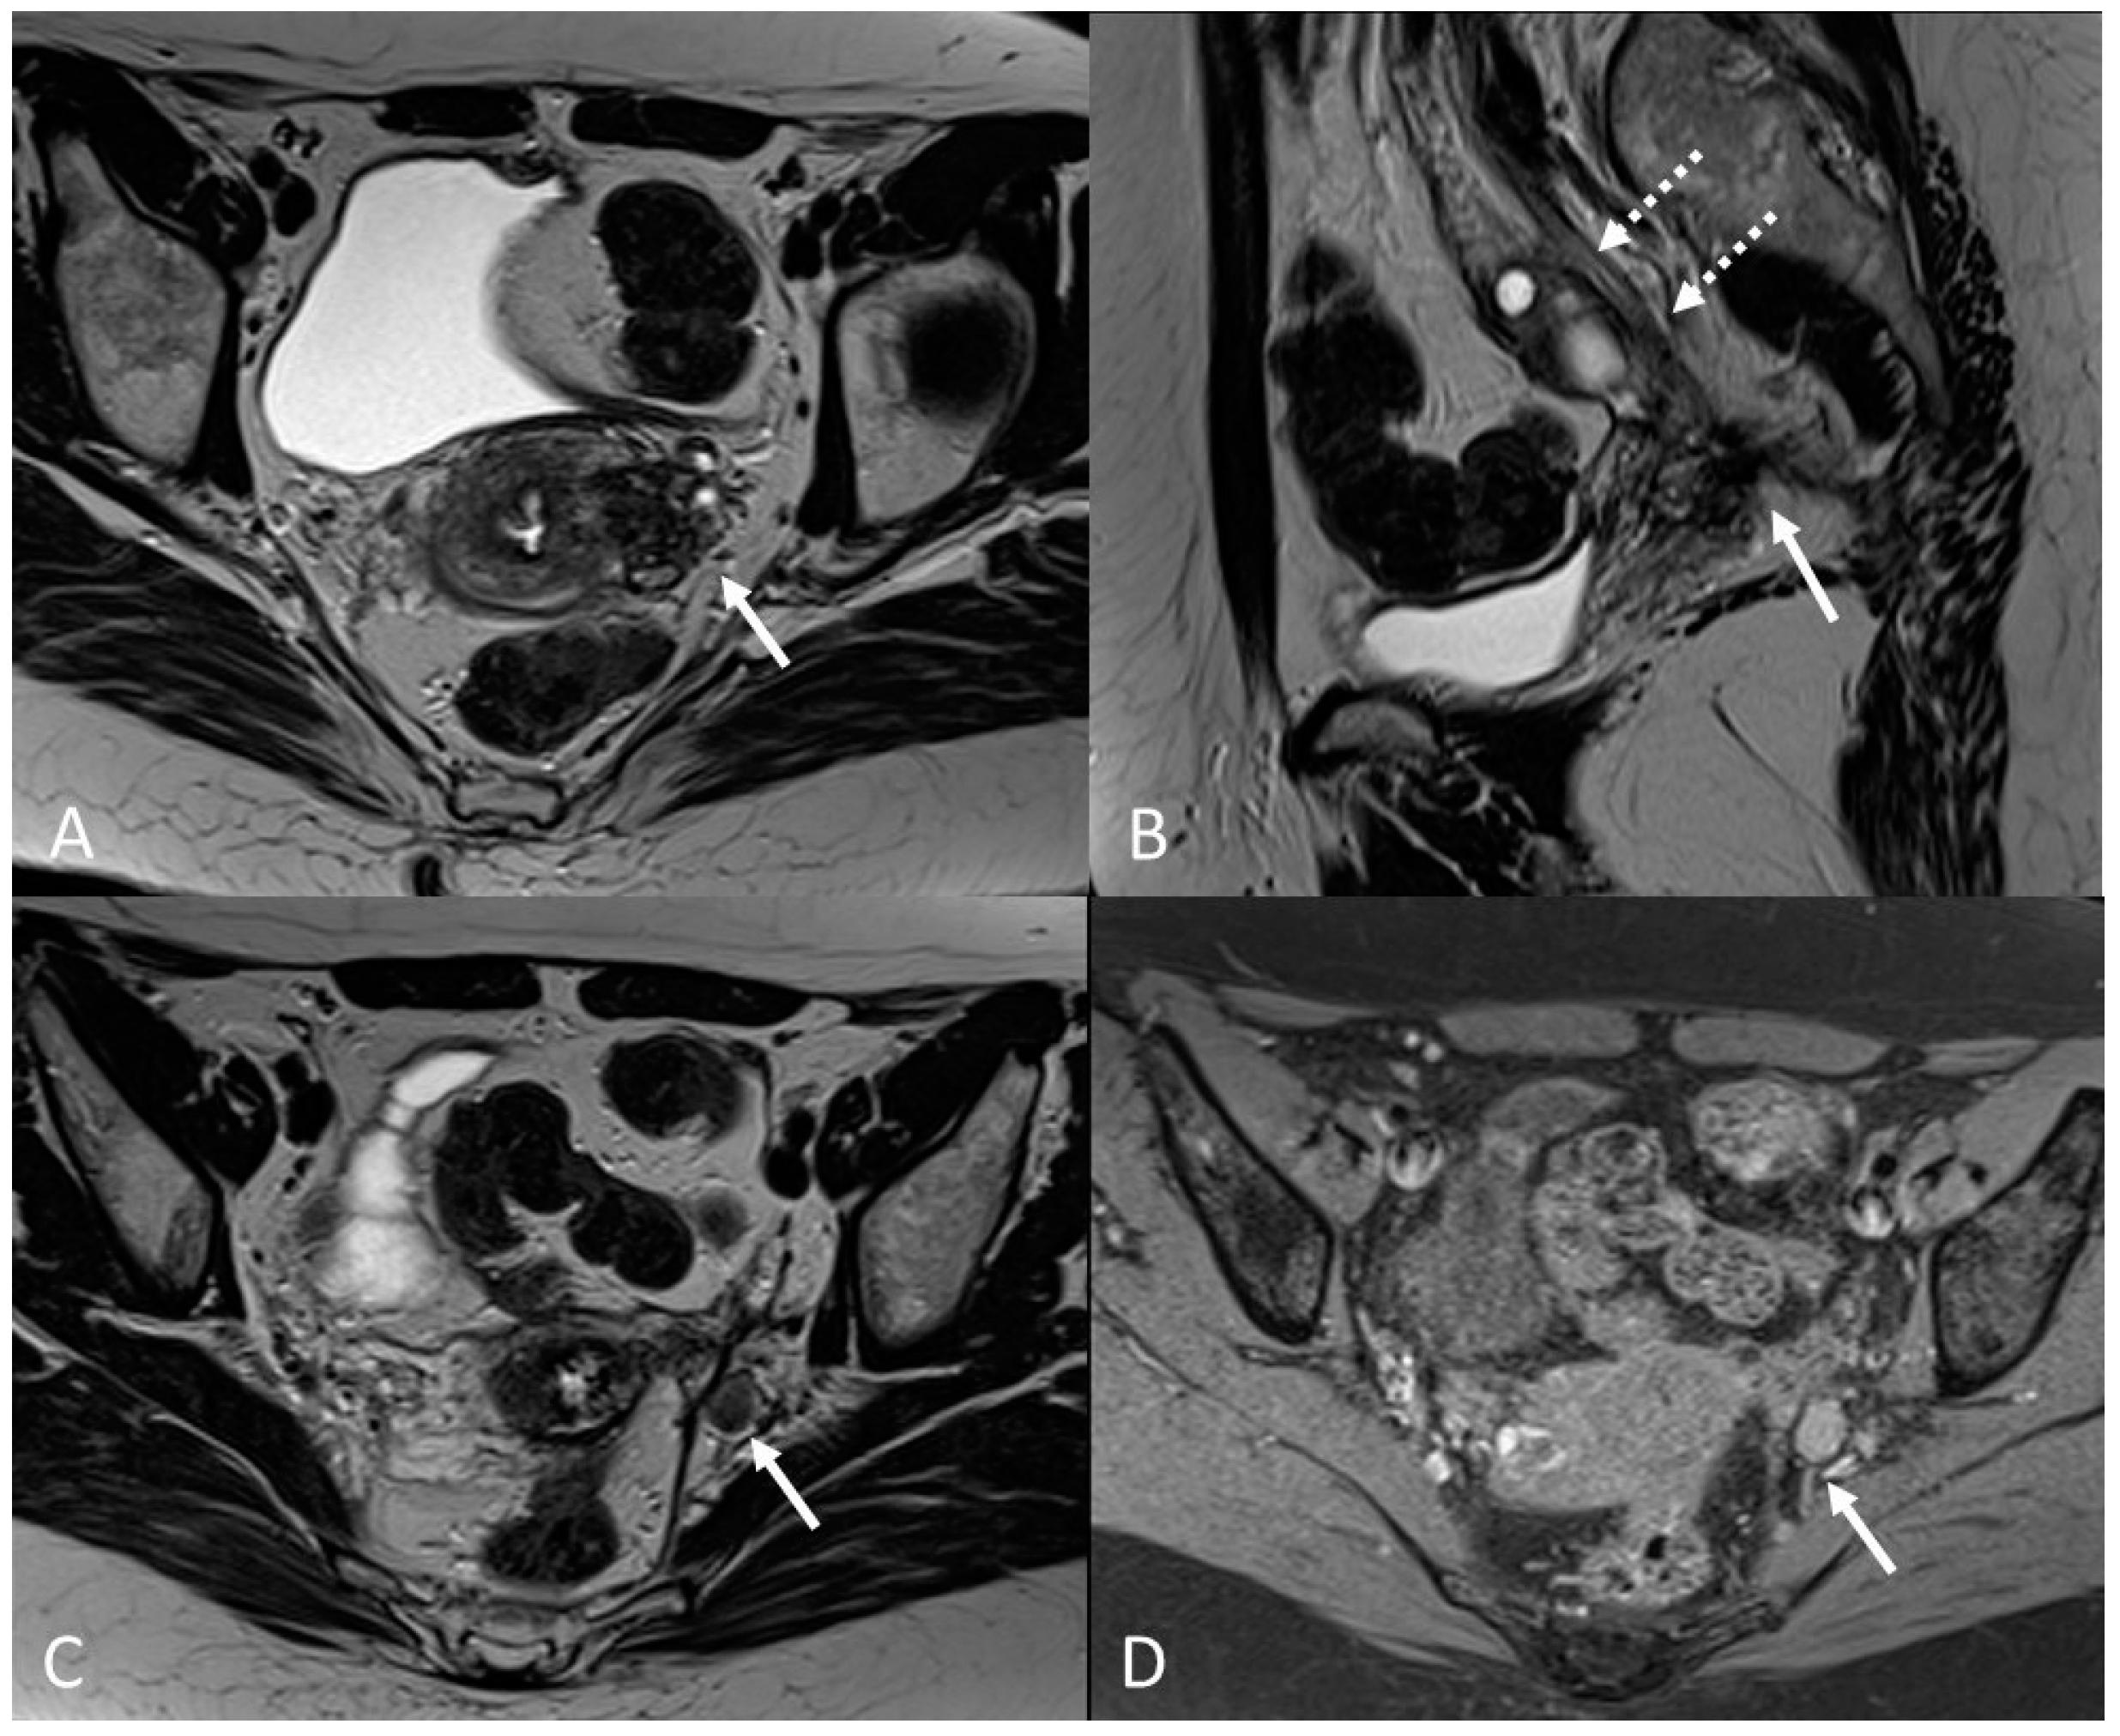

3.2.5. Rectosigmoid Colon

3.2. Deep Infiltrating Endometriosis (DIE)